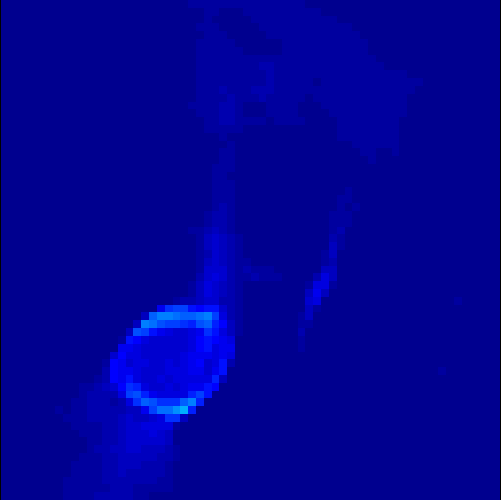

5.2 Monte Carlo Simulation

In order to test the behaviour of the proposed method in a more realistic, random-based test case, we performed a Monte Carlo simulation for dynamic SPECT imaging. First, we created a simple image phantom consisting of an outer and two inner circles which represents the structure of the region of interest (see figure 8(a)). Within those regions we assumed concentration curves over a time period of 90 time steps as displayed in figure 8(b). Based on the tracer intensity in an image frame at each time step, we created a variable number of random decay events (where the number is proportional to the average concentration in one pixel in the whole image frame per time step) with a probability proportional to the concentration in every subregion. They are detected by a virtual double head gamma camera rotating around the patient by 46 degrees per time step, which consists of 374 detector bins. Every simulated decay event is projected onto the scanner and counted by the corresponding detector bin.

In two different tests we fixed the number of events counted by the detector equal to (resp. ) times the average concentration in one pixel. The resulting sinogram images of the accumulated counts in each bin are shown in figure 9.

Based on the sinogram data we applied the proposed algorithm in order to reconstruct the original image sequence. The results for both test cases are shown in figure 10.

As one can see, the method is able to reconstruct the regions properly, even in case of a low count number. Within a number of iterations (average of 100 outer and 10000 inner iterations), the algorithm presents a reasonable reconstruction of the region of interest and the corresponding regional tracer concentration curves. Here, the parameters were not optimized as in the case of the synthesized data sets in the previous section, but kept fixed as , and . With futher optimized parameter values one could possibly provide even better results.